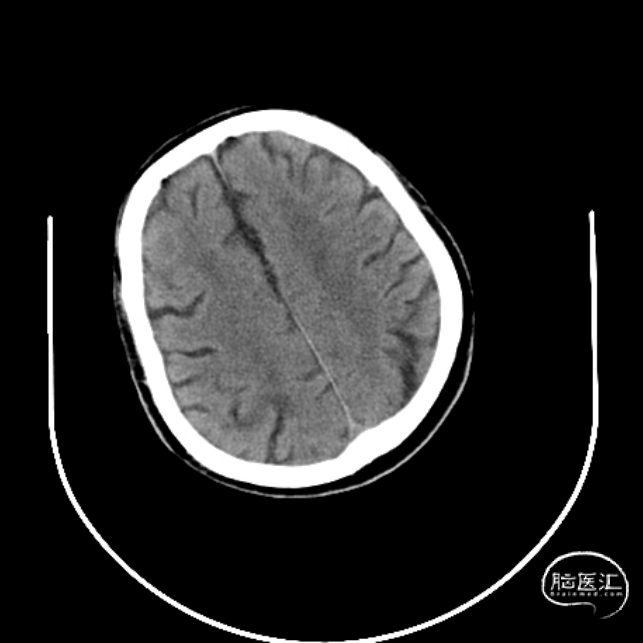

术前CT

术后24小时CT示

术后24小时查体:神清,言语欠清,双侧瞳孔等大正圆,直径3.0mm。直接间接对光反射灵敏,双眼各向活动正常,右侧鼻唇沟浅,伸舌右偏,左侧肢体肌力5级,右侧上肢3级,下肢肌力4级,右侧巴氏征阳性。急诊NIHSS评分:5分。